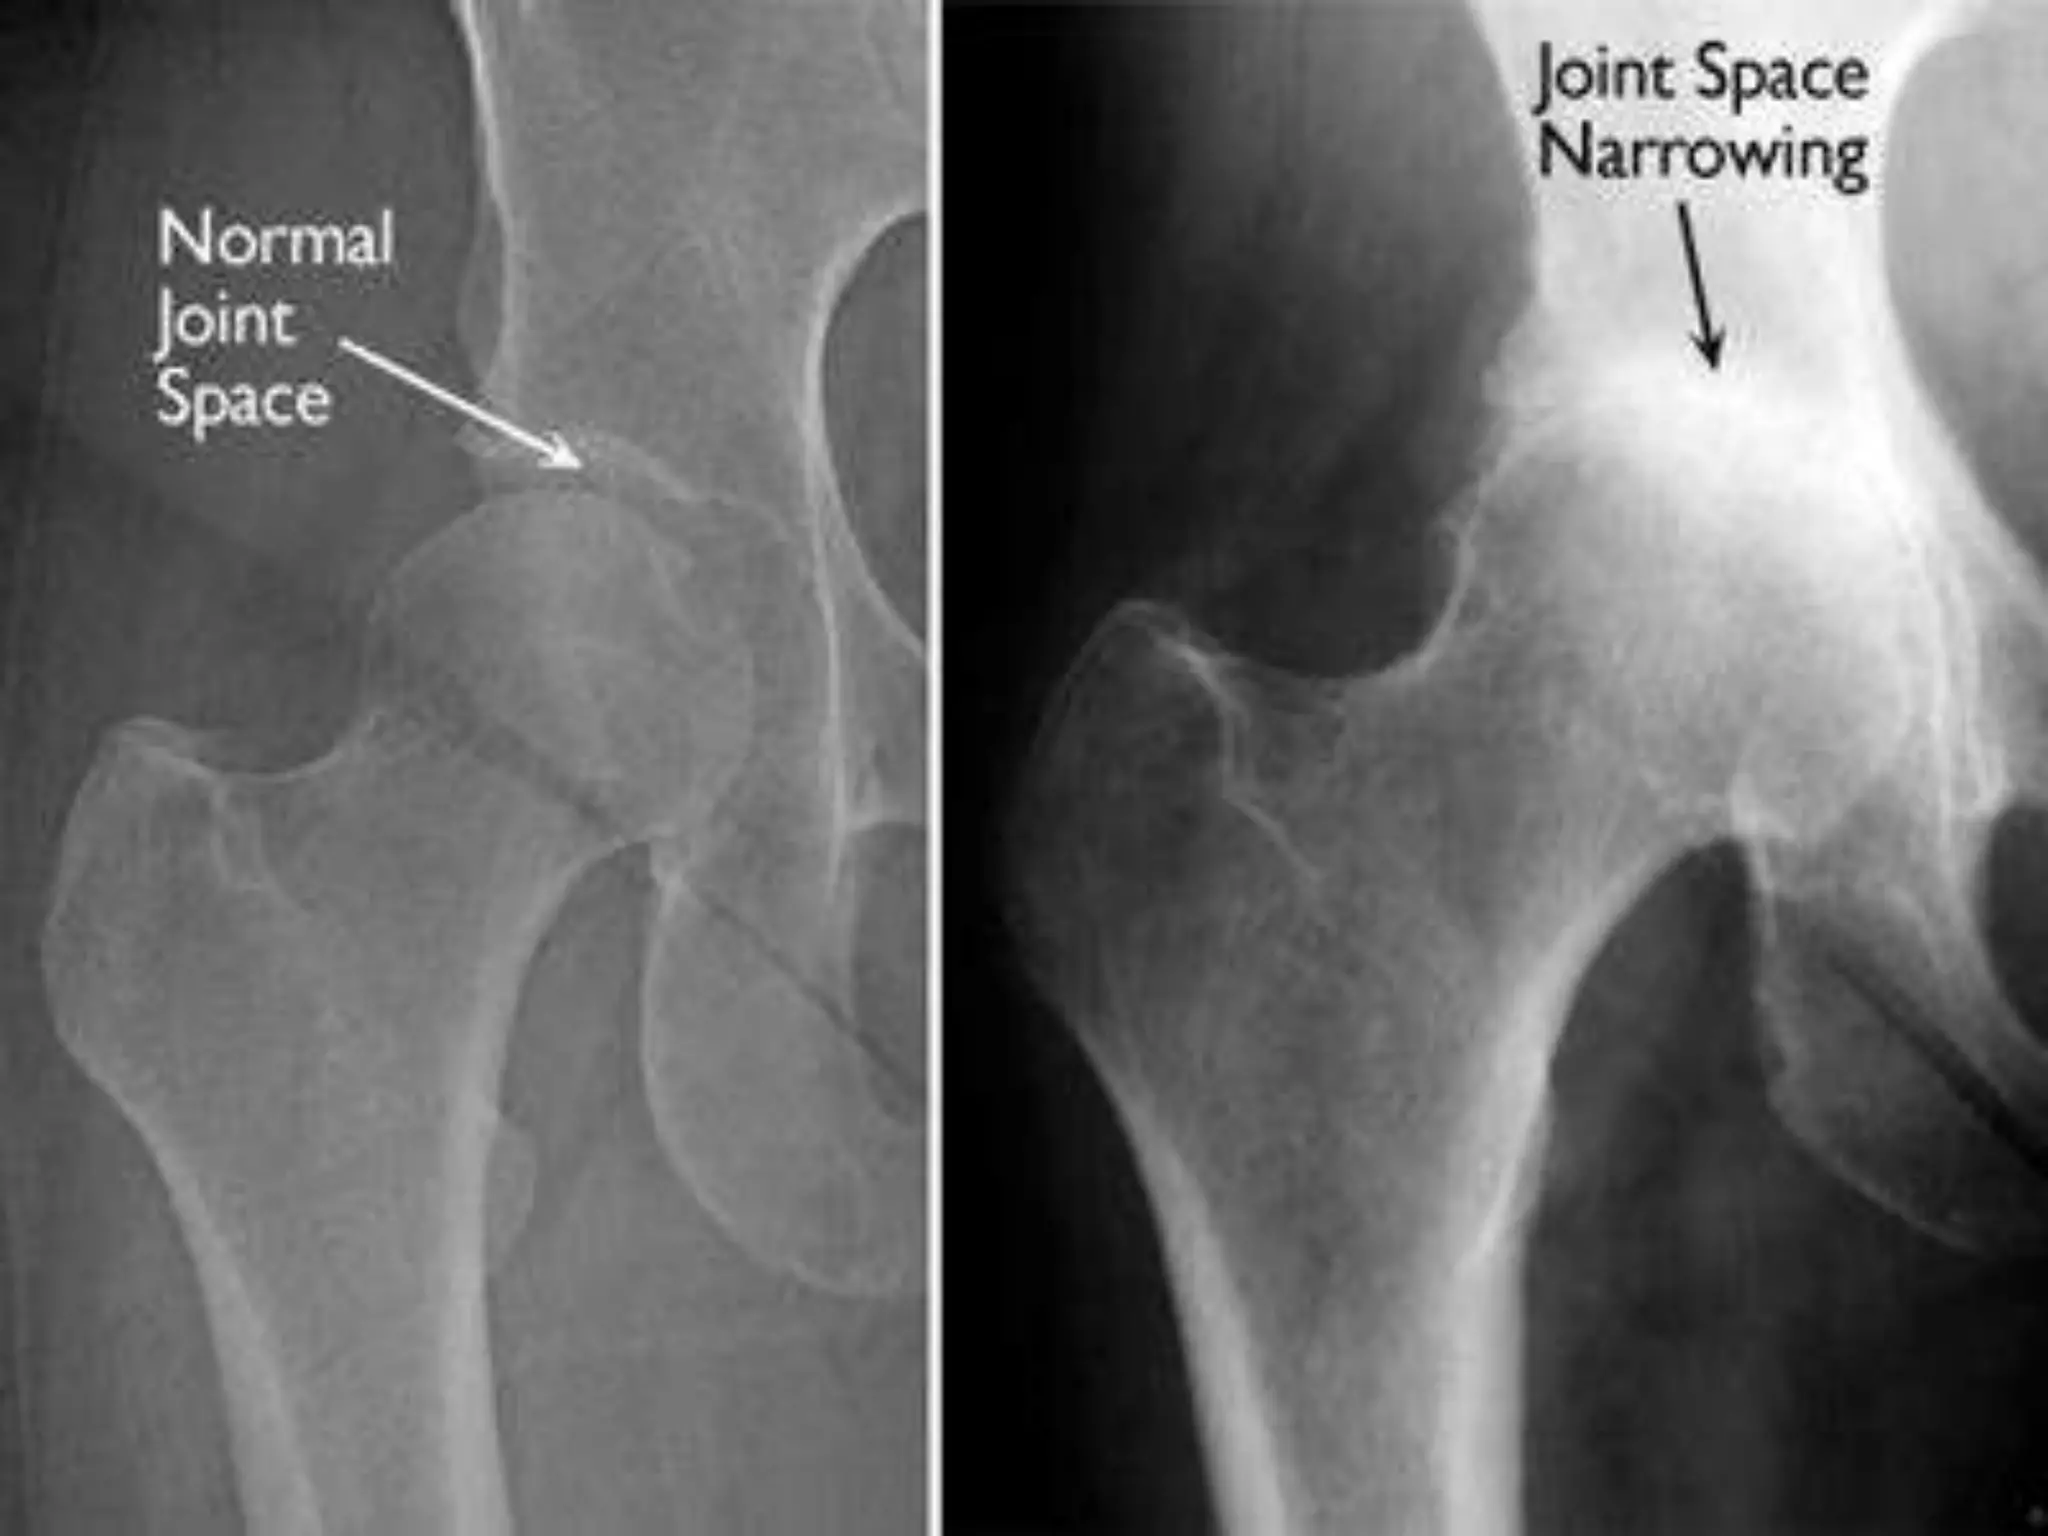

3.Arthritis

• Arthritis is a common cause of pathological

gait. An arthritic hip has reduced range of

movement during swing phase which causes

an exaggeration of movement in the opposite

limb ‘hip hiking’.